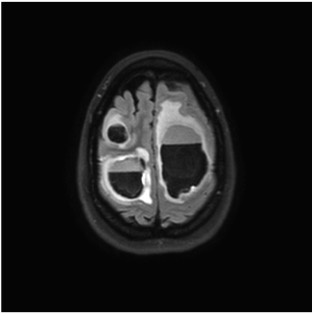

View Hippocampal Sparing Whole Brain Radiotherapy Pics. Improved plan quality with automated radiotherapy planning for whole brain with hippocampus sparing: Hippocampal sparing whole brain radiotherapy vs conventional whole brain radiotherapy in patients with brain metastases.

Whole brain radiotherapy with hippocampal avoidance and simultaneously integrated brain metastases boost:

Additionally, simultaneous integrated boost (sib) on individual metastases may further improve the outcome. Further trials are needed to evaluate the use of neurocognitive protective agents and hippocampal sparing with wbrt. Considerations from the uk hippo trial qa programme. The british journal of radiology, 2017.